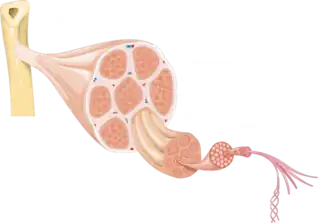

In animal and Human biology, a tendon cell is a cell that makes up tendons, the bands of connective tissue that connects muscles to bones. Tendon cells, also known as tenocytes or tendon fibroblasts, are specialized cells that contribute to the structure, function, and repair of tendons in the body. Tendons are fibrous tissues that connect muscles to bones, and tendon cells play a vital role in maintaining tendon homeostasis and facilitating healing following injury.

Tendon cells are primarily responsible for the production and maintenance of the tendon extracellular matrix (ECM), which consists mainly of collagen fibers. These cells are involved in synthesizing collagen and other ECM components that provide tendons with tensile strength. Tendon cells also participate in remodeling the ECM in response to mechanical stress and injury.

Structure[1]

Tendon cells are typically elongated, spindle-shaped cells that align along the axis of tendon fibers. They contain large amounts of rough endoplasmic reticulum to support the production of collagen. The unique structure of tendon cells allows them to withstand mechanical stress and contribute to tendon strength and flexibility.

Vertebrates

Tendon cells, or tenocytes, are elongated fibroblast type cells. The cytoplasm is stretched between the collagen fibres of the tendon. They have a central cell nucleus with a prominent nucleolus. Tendon cells have a well-developed rough endoplasmic reticulum and they are responsible for synthesis and turnover of tendon fibres and ground substance.